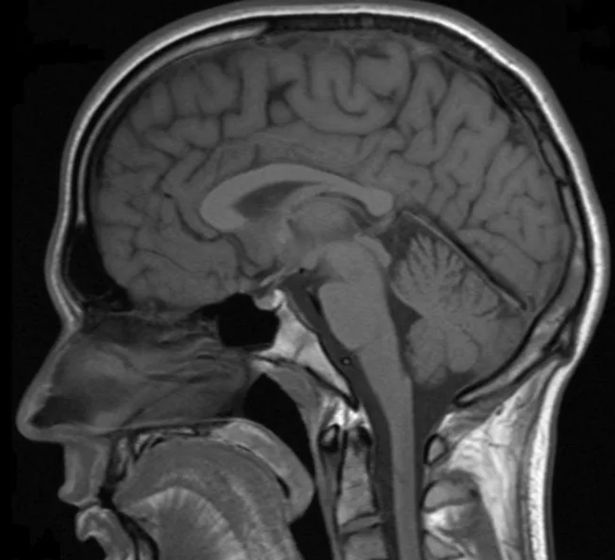

8. Hình ảnh minh họa